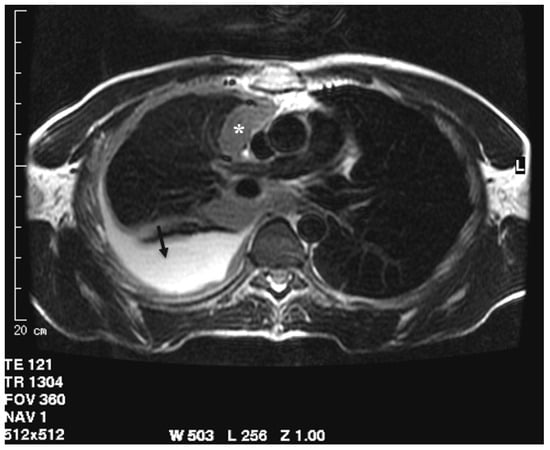

Figure 1.

Axial CT scan after contrast administration reconstructed with smooth kernel with mediastinal windows demonstrates circumferential pleural nodular thickening with mediastinal pleura involvement (asterisk) and pleural effusion (arrow).